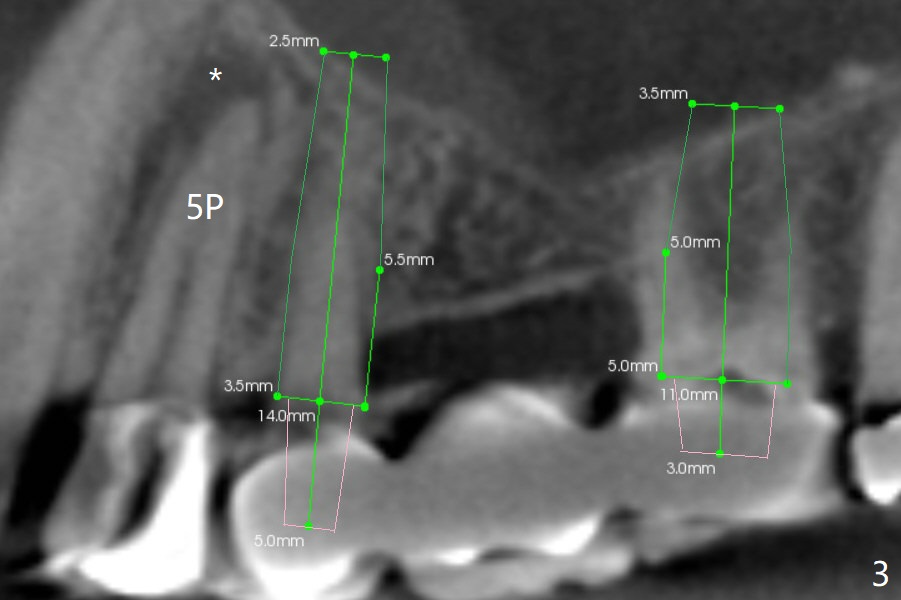

A 64-year-old man requests implant restoration after the upper FPD dislodges (Fig.1). The measurement of the septal height at #2 by PA (Fig.2) is not as precise as CBCT (Fig.11, taken 4 years earlier). There appears to be 2.8 mm bone apical to the tooth #4 (Fig.2); in contrast, the bone is more or less buccal and palatal to the root apex shown by CT (Fig.5). Furthermore CT more clearly shows apical lesions of the tooth #5 (Fig.3,4) than PA (Fig.2). In addition to pulpal test, RCT should be done for #5 prior to implant placement at #4.

After extraction of the tooth #4, osteotomy is initiated in the middle of the palatal slope (Fig.6), followed immediately by change in trajectory (Fig.7). The depth of the osteotomy is ~ 5 mm (Fig.8), followed by 2.8 mm round bur from Sinus Lift Master Kit. Press the burs palatally. Following Vanilla Graft (red circles), place a 3.5 or 4.0x17 mm dummy and final implants (Fig.3,9,10).

Sinus lift at #2 is relatively easy because osteotomy is not to be done in a slope (Fig.3,11,12).